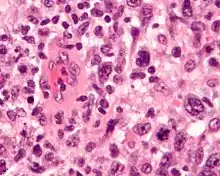

Micrograph of an anaplastic large-cell lymphoma. H&E stain.